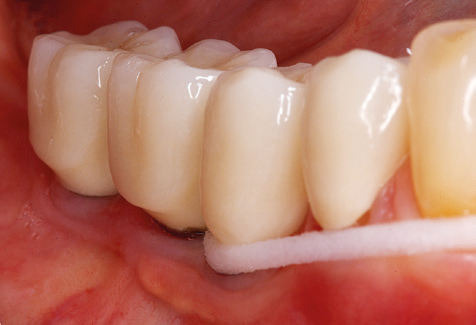

A 52-year-old patient presented in our clinic for the first time in 2004 following tooth loss in the third quadrant, expressing a desire for a new prosthetic restoration. Periodontal and radiological diagnostics revealed the need for extensive periodontological treatment. In addition, teeth 48, 28 and 27 were attributed a very poor prognosis and were subsequently extracted (Fig. 1). Following the successfully completed, systematic periodontological treatment, a fixed dental implant was inserted with the introduction of five implants in tooth regions 35, 36, 37, 46 and 47. Prosthetic treatment of the natural teeth was effected with veneered zirconium dioxide ceramic crowns; the implants were composed of two-piece, individual zirconium dioxide abutments and similarly veneered crowns made of a zirconium dioxide ceramic (Cercon base colored, Dentsply Sirona Lab). Definitive insertion of the prosthetic restoration occurred in 2005.

Due to the presence of periodontal disease, SPT was performed every three months in the first years following the insertion. The patient demonstrated a high degree of motivation and good compliance. The pocket depths recorded annually revealed a stable periodontal situation with a BOP index of below five per cent. On the basis of the stable periodontal situation and good cooperation on the patient’s part, the recall interval was extended to every six months as of the sixth year of the prosthetic function phase. Following the change in the recall interval, the respective annual documentation of the periodontal status continued to reveal a stable periodontal situation with no increase in the pocket depths and a BOP index below five per cent (Fig. 2a and b).

The ten-year check-up revealed no indications of advancing clinical attachment loss or peri-implant bone substance loss (Fig. 3).